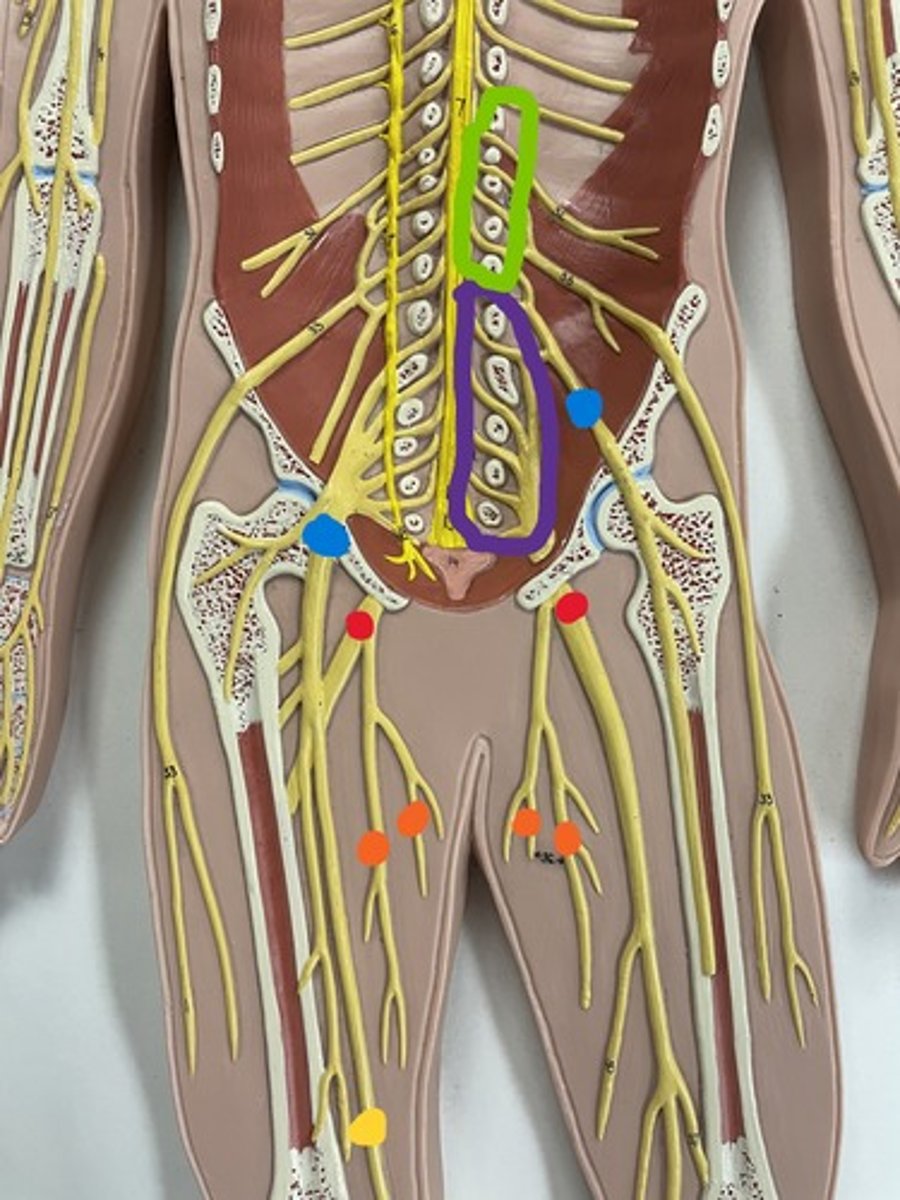

Lumbar plexus

Lumbar plexus

green

Femoral nerve

purple

Femoral nerve

blue

Obturator nerve

yellow

Obturator nerve

orange

Saphenous nerve

yellow

Sacral plexus

purple

Sacral plexus

red

Sciatic nerve

red

Tibial nerve

red

Common fibular nerve

blue